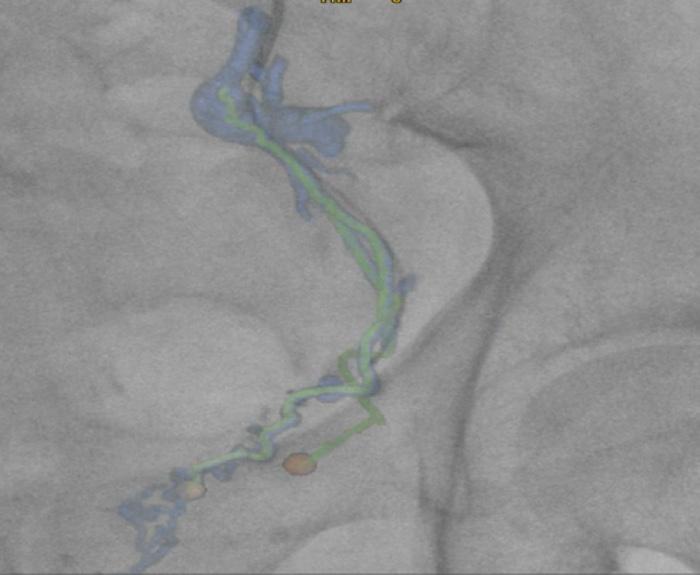

The incidence of lung cancer has increased considerably in the last few decades with the lung as the most common site of metastatic involvement. Despite the improvements in the diagnosis and treatment for malignant lung tumours, the prognosis of the patients is still unsatisfactory.1 Currently, locoregional chemotherapeutic techniques such as transpulmonary chemoembolization (TPCE) for the treatment of lung malignancies have gained increasing importance. The purpose of this retrospective study was to evaluate local tumour response and patient survival after the treatment of pulmonary metastases using TPCE as a palliative treatment method.

In TPCE, a 5 French (Fr) endovascular sheath and 5Fr headhunter catheter are routinely placed transfemorally under fluoroscopy until the pulmonary artery and subsequently the tumourfeeding segmental pulmonary branch are reached. A balloon catheter (up to 7mm in diameter) is optionally placed for better results.2 This selective pulmonary artery catheterisation results in a blockage of the arterial supply to the tumour tissue, resulting in regional ischaemic necrosis in the target tumour tissues while reducing damage to the surrounding normal lung parenchyma. Thereafter, mitomycin

and gemcitabine as chemotherapeutic agents are administered in combination with an embolization of lipiodol and microspheres. This extends the storage time of the injected cytostatics in the tumours and reduces the outflow into

the circulatory system.3 Consequently, the frequency and severity of systemic effects are limited. Other occlusion materials used are coils, polyvinyl alcohol, degradable starch microspheres, and gelatin sponges.

In our study, 223 patients (138 women, 85 men; mean age: 59.3±11.9 years) with unresectable lung metastases and/or not responding to systemic chemotherapy received repetitive TPCE (mean number of sessions 4.7±3.7) between January 1990 and May 2021. Patients had predominant lung metastases and in most cases with bilateral lung involvement. Origin of the metastases were either colorectal carcinoma (n=139) or breast cancer (n=84). Tumour-supplying vessels were catheterised selectively in order to apply chemotherapeutic agents locally, combined with lipiodol and microspheres. The response was assessed according to the revised RECIST criteria.

Of the evaluated 183 cases, partial response was achieved in 4.9% (n=9), stable disease in 62.3% (n=114), and progressive disease in 32.8% (n=60) of the patients. Mean and median overall survival time were 23.5 and 14 months, respectively.

TPCE can be used as a palliative treatment in unresectable lung malignancies to reduce the tumour burden or to achieve local tumour control,4 or as a neoadjuvant or curative treatment option combined with thermal ablation such as radiofrequency ablation (RFA) and microwave ablation (MWA) (Figure 1).5,6